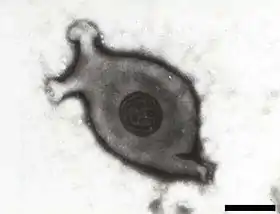

مفطورة منتنة للدجاج (الاسم العلمي: Mycoplasma gallisepticum) هي نوع من البكتيريا تتبع جنس المفطورة من فصيلة المفطورات.[1]